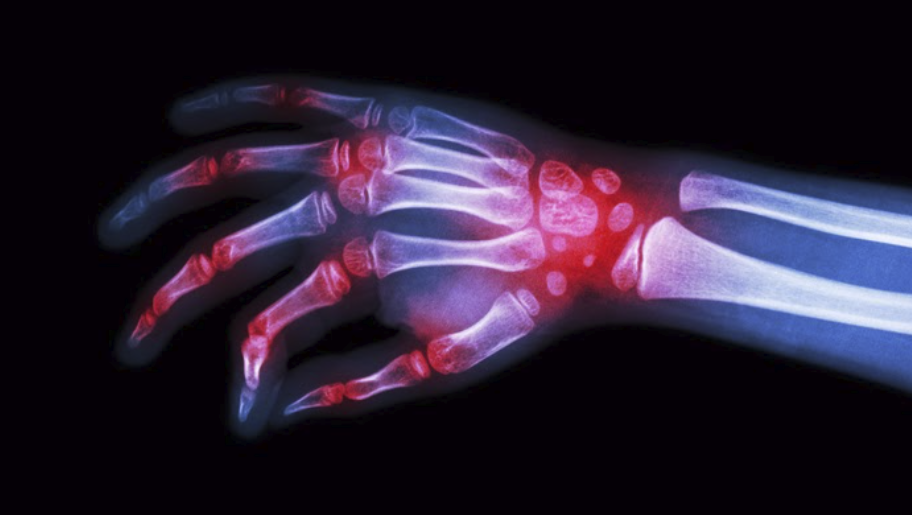

How Diet and Supplements Can Help Rheumatoid Arthritis

Rheumatoid arthritis (RA) is a chronic, autoimmune, inflammatory disease that affects the whole body and leads to cartilage, joint, and bone destruction. RA is a very debilitating disease that may lead to difficulty doing daily activities. The pain and stiffness can be frustrating and challenging. Two percent of the global population suffers from this disease; […]